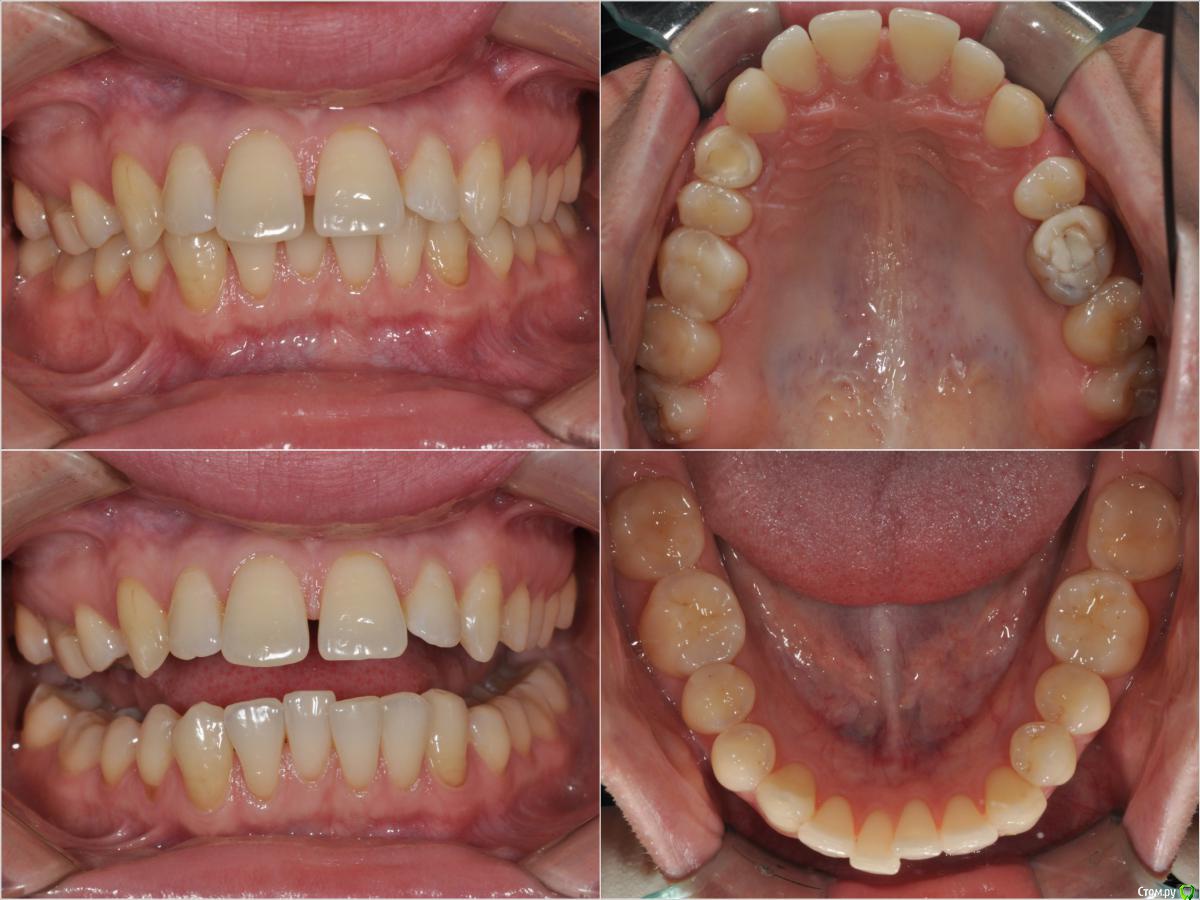

losenok83 Опубликовано 11 мая, 2016 Поделиться Опубликовано 11 мая, 2016 Здравствуйте! Мне 32 года. Год в брекетах. Уже больше 3-х месяцев беспокоит боль в в суставе, при открывании рта, иногда при жевании. До брекетов у меня хрустел сустав с левой стороны, сейчас хрустит с обеих сторон+ закладывает периодически уши. Лечусь с удалением 4-рок на ВЧ. Справа 4-ка была удалена в детстве по орт.показаниям , слева вначале нынешнего лечения. Не связана ли боль в суставе с удалением 4-рок? Действительно ли нужно было их удалять? Не нужно ли было выдвигать нижнюю челюсть вперед спец. аппаратами? И что можно сделать сейчас? Фото и снимки до лечения. Ретинированная 8-ка удалена. Ссылка на комментарий

losenok83 Опубликовано 4 сентября, 2016 Автор Поделиться Опубликовано 4 сентября, 2016 Здравствуйте, очень нужна ваша помощь снова! Я обошла много ортодонтов в своем городе на предмет дальнейшего лечения. В конце концов мое самочувствие более менее менее улучшилось только после ортотика. В дальнейшем мне сказали ортодонт поставит мои зубы на такую высоту. Скажите пожалуйста это правда возможно, на такую высоту вытянуть свои верхние и нижние зубы? И еще изначально этот ортодонт планировала что в этом ортотике Н,Ч, выйдет вперед , а потом ее расширят. Поскольку этого не произошло, сказала что просто раздвинут место для раннее удаленных 4-рок на В,Ч. пружинами. А я очень боюсь, что в результате зубы будут торчать вперед как раньше.Разве нет? Расчет ТРГ на данный момент лечения. И вид челюстей в ортотике. Ссылка на комментарий